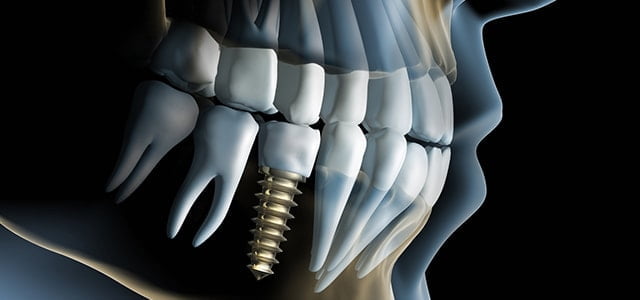

インプラントとは何ですか?歯科用インプラントとは、チタンでできた人工歯根のことです。インプラント治療では、このインプラントを顎の骨に埋め込み、先端に人工歯を装着することで歯を補います。入れ歯よりも自然に近い咬み心地が得られます。

骨に付くのですか?インプラント体はチタン製ですので、骨と結合します。